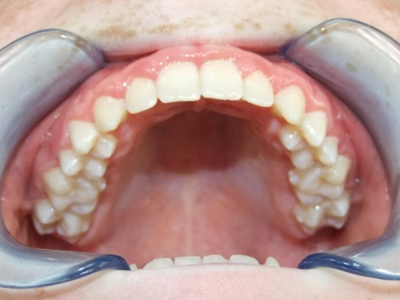

eindfoto

Leeftijd bij aanvang: 9 jaar

1-6 Bonded Hyrax + partieel vast onderkaak + TransForce onderkaak

7-13 Twinblock

13-22 volledig vast onder- en bovenkaak + rotator

Retentie: wrap en c-c bar

Leeftijd bij retentie: 12 jaar